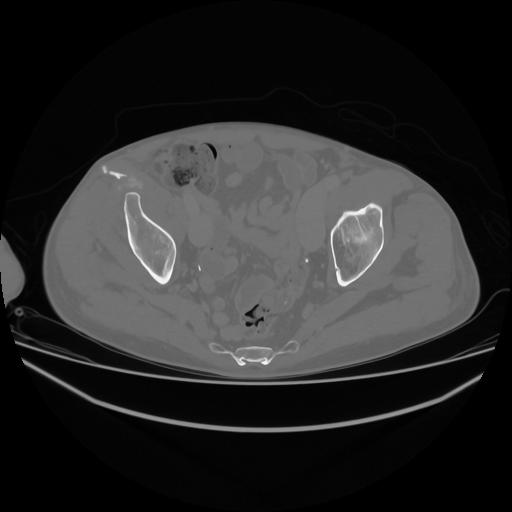

5 CUERPO,CE,Vol,1.0,CUERPO,,